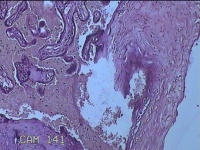

胎盘组织

胎膜早破 早产

停经36+1周,阴道流液3天。

灰白暗红色胎盘组织18x15.5x2.3㎝一个,表面光滑,血管清晰,颜色发暗,绒毛面结节状,轻度糜烂,表面有少许凝血块,切面见绒毛内有部分淤血,边缘蜕膜可见多个小血肿,脐带15x1.5x0.8㎝,切断脐带,见脐血管内有凝血块。